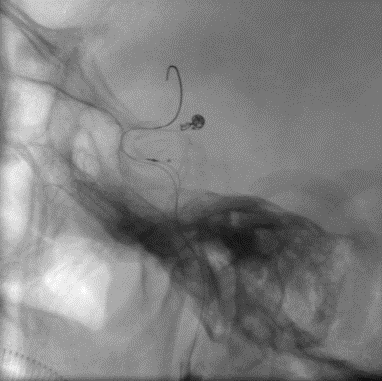

10. 术后复查造影可以看到,动脉瘤实现Raymond I级栓塞,CT复查也没有异常。希望这个病人能有个好的预后,也期待这个病例的随访结果。

Final

术后CT